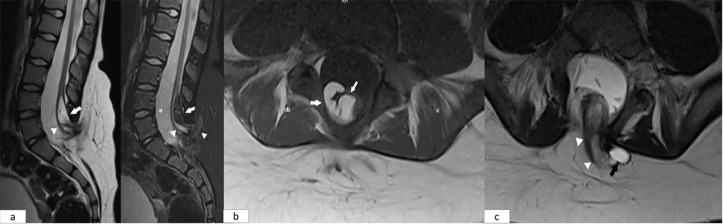

Unusual Comorbid Condition in a Child with Severe Factor XI Deficiency: Spina Bifida

严重因子XI缺乏儿童的不寻常合并症:脊柱裂。